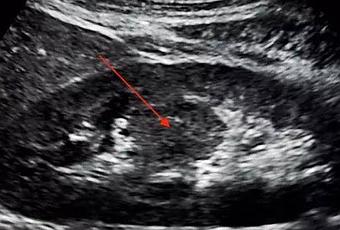

La columna prominente de Bertin es una variante anatómica común que se presenta como una extensión “parecida a una masa” del tejido cortical renal entre las pirámides de la médula renal. Prominente o también conocida como hipertrofiada, la Columna de Bertin no tiene importancia clínica, sin embargo, puede llegar a ser de importancia radiográfica debido a su tendencia a imitar una masa renal.